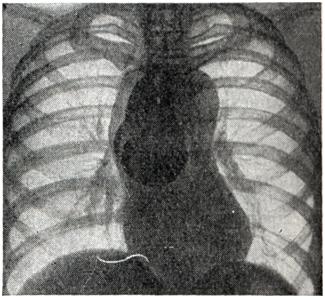

Аневризмы восходящей аорты обычно хорошо определяются в виде выпячиваний на правом контуре сосудистой тени в прямой проекции (рис. 3) и на переднем контуре — в левом косом и боковом положениях. Гораздо реже аневризма располагается на левой стенке восходящей аорты и образует выпячивание слева. Аневризмы дуги аорты (рис. 4) в прямой проекции обычно имеют вид массивной тени над изображением сердца, а в левом переднем косом положении проецируются на область дуги аорты. Аневризмы нисходящей аорты дают добавочные тени по левому контуру сосудистой тени (книзу от первой дуги) в прямой проекции и проецируются на ретрокардиальное пространство и тень позвоночника в косых положениях. Бывают множественные аневризмы аорты. Дифференциальный диагноз аневризмы аорты с опухолями и кистами средостения представляет большие трудности. Признак пульсации имеет лишь ограниченное значение: она может быть передаточной при опухолях и отсутствовать при тромбированной аневризме или сращениях. Рекомендуется применение томографии и пневмомедиастинографии. Кроме обычно встречающихся вторичных признаков — смещения пищевода и трахеи, возможна картина ателектаза легкого вследствие сдавления бронха, высокое положение диафрагмы из-за давления на диафрагмальный нерв, обеднение кровотока в легком ввиду сдавления легочного ствола, атрофия от давления тел позвонков, ребер (рис. 5). Рентгенологическое распознавание аневризмы брюшной аорты по обычным снимкам возможно лишь при наличии обызвествления стенок аорты или типичной деструкции тел позвонков. В предоперационном диагнозе всех аневризм аорты решающее значение имеет аортография.